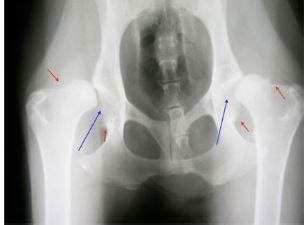

- Dysplázia bedrového a lakťového kĺbu (DBK a DLK): Toto dedičné ochorenie spôsobuje nesprávne zapadanie kĺbov, čo vedie k degeneratívnej artritíde, bolestiam a problémom s pohybom. V prípade bedrového kĺbu ide u stredne veľkých a veľkých psov spravidla o genetické predispozície. Stehenná kosť nezapadá do panvovej jamky, čo spôsobuje u psa krívanie, bolesti alebo obmedzuje jeho pohyb. Dysplázia lakťového kĺbu býva zapríčinená rýchlym rastom kostí u jedinca. Taktiež môže ísť o dedičné ochorenie. Tým, že kosti a kĺby dorastajú odlišnou rýchlosťou, dochádza k nesúmernosti, čo môže spôsobovať laxnosť kĺbov, krívanie alebo limitovaný pohyb.